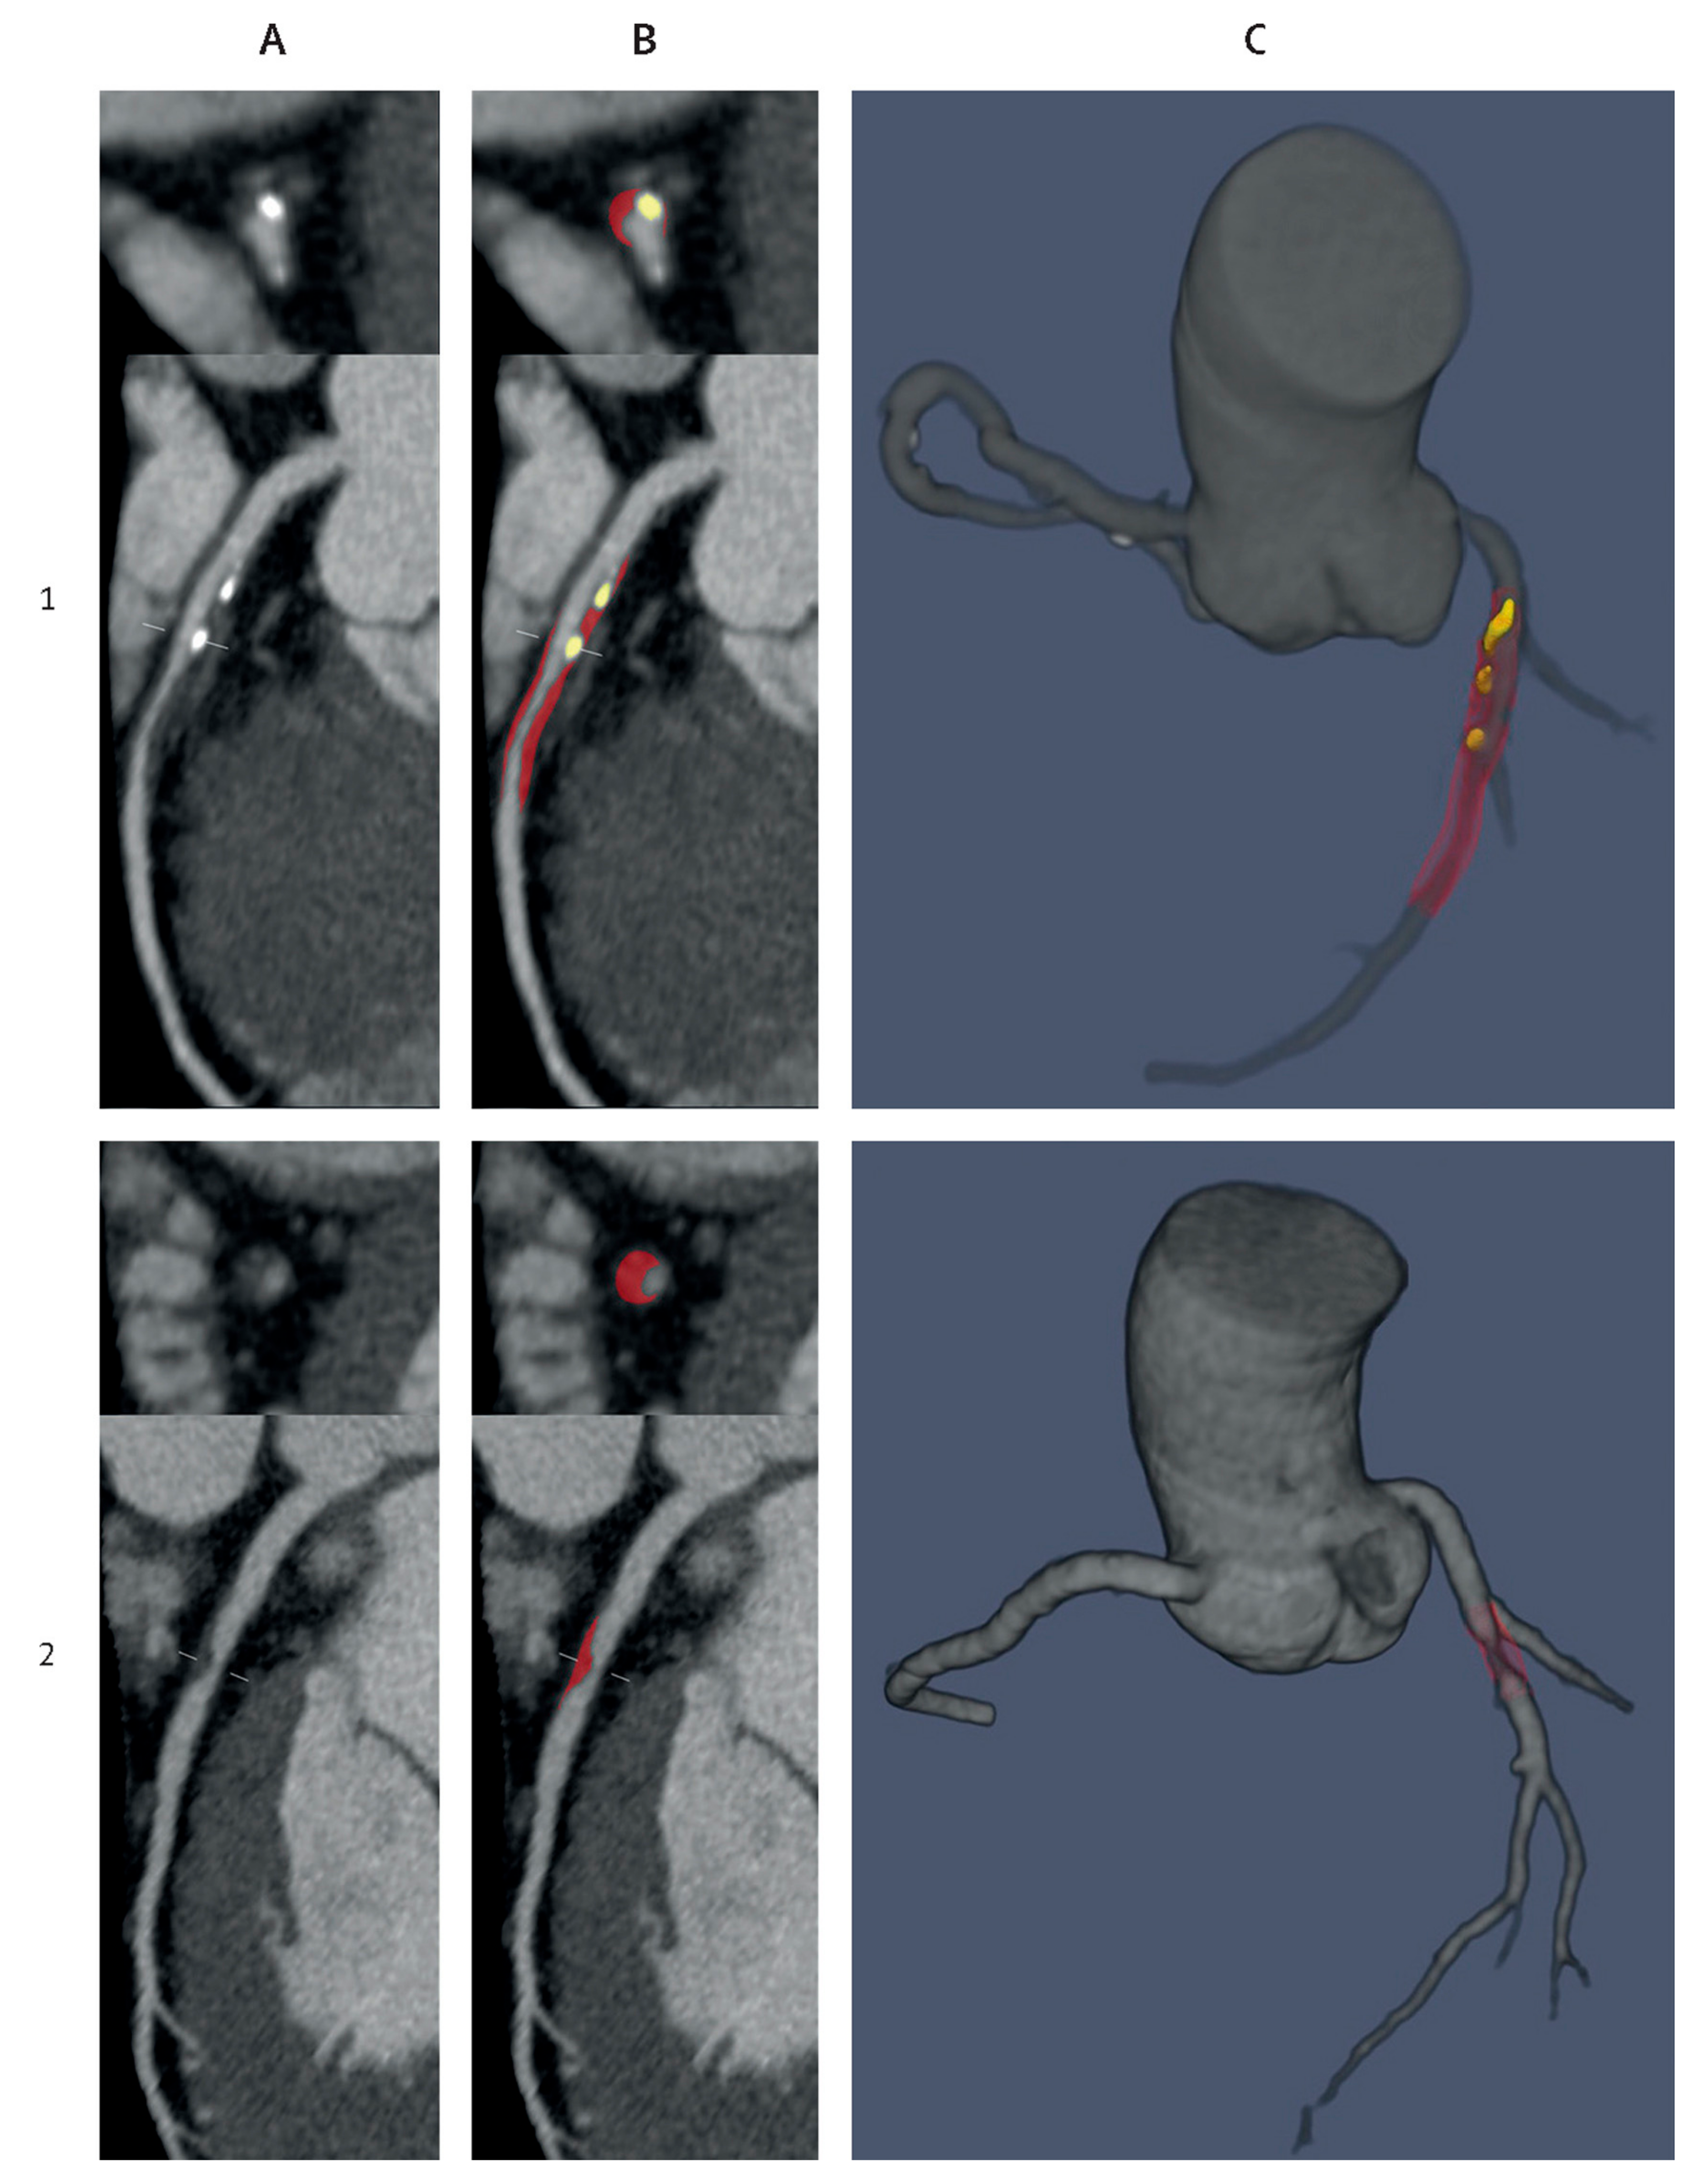

- Raffort, J.; Adam, C.; Carrier, M.; Ballaith, A.; Coscas, R.; Jean-Baptiste, E.; Hassen-Khodja, R.; Chakfé, N.; Lareyre, F. Artificial intelligence in abdominal aortic aneurysm. J. Vasc. Surg. 2020, 72, 321–333.e321. [Google Scholar] [CrossRef]

- Lareyre, F.; Adam, C.; Carrier, M.; Dommerc, C.; Mialhe, C.; Raffort, J. A fully automated pipeline for mining abdominal aortic aneurysm using image segmentation. Sci. Rep. 2019, 9, 13750. [Google Scholar] [CrossRef] [PubMed]

- Spinella, G.; Fantazzini, A.; Finotello, A.; Vincenzi, E.; Boschetti, G.A.; Brutti, F.; Magliocco, M.; Pane, B.; Basso, C.; Conti, M. Artificial Intelligence Application to Screen Abdominal Aortic Aneurysm Using Computed tomography Angiography. J. Digit. Imaging 2023, 36, 2125–2137. [Google Scholar] [CrossRef] [PubMed]

- Attallah, O.; Karthikesalingam, A.; Holt, P.J.; Thompson, M.M.; Sayers, R.; Bown, M.J.; Choke, E.C.; Ma, X. Using multiple classifiers for predicting the risk of endovascular aortic aneurysm repair re-intervention through hybrid feature selection. Proc. Inst. Mech. Eng. Part H 2017, 231, 1048–1063. [Google Scholar] [CrossRef] [PubMed]

- Wise, E.S.; Hocking, K.M.; Brophy, C.M. Prediction of in-hospital mortality after ruptured abdominal aortic aneurysm repair using an artificial neural network. J. Vasc. Surg. 2015, 62, 8–15. [Google Scholar] [CrossRef] [PubMed]

- Lee, R.; Jarchi, D.; Perera, R.; Jones, A.; Cassimjee, I.; Handa, A.; Clifton, D.A.; Bellamkonda, K.; Woodgate, F.; Killough, N.; et al. Applied Machine Learning for the Prediction of Growth of Abdominal Aortic Aneurysm in Humans. EJVES Short Rep. 2018, 39, 24–28. [Google Scholar] [CrossRef]